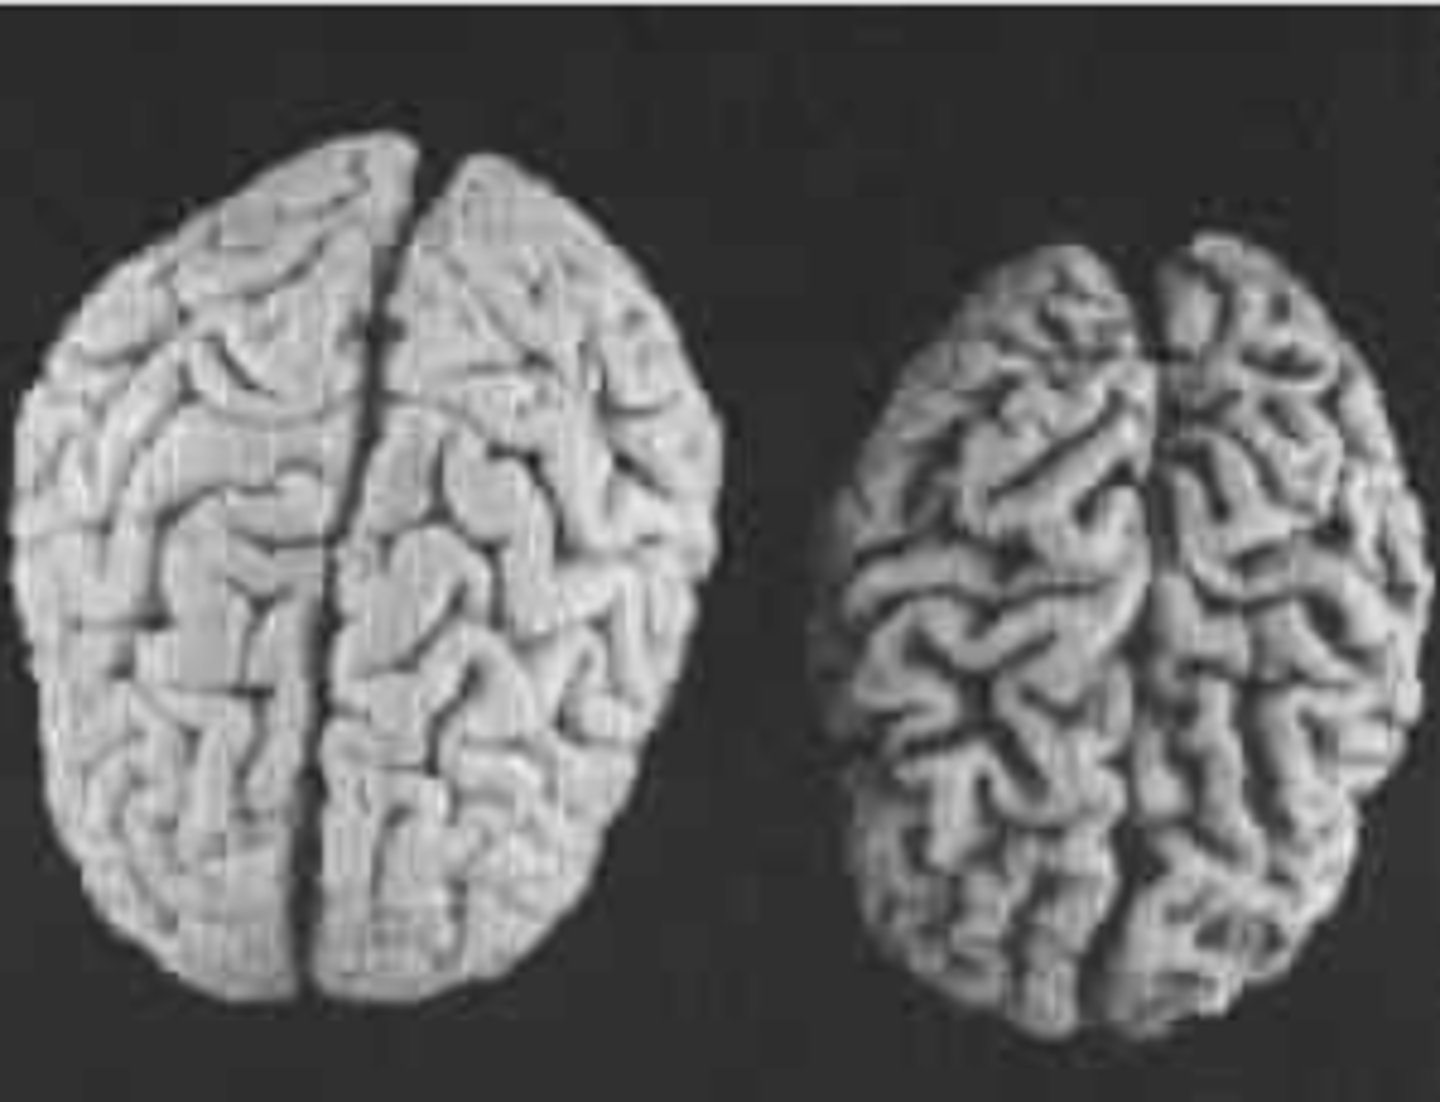

What structural changes in the brain are occurring with dementia?

Cells are shrinking and dying